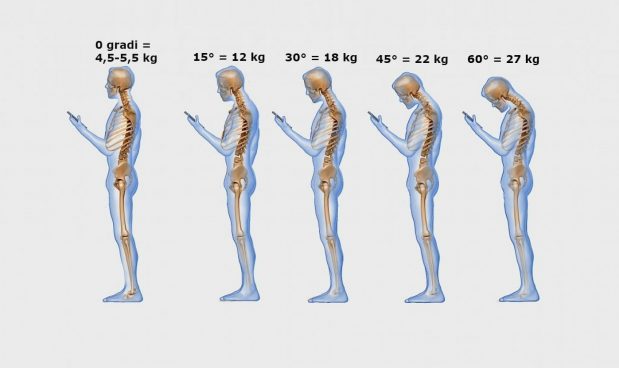

Rintanarsi nel proprio mondo virtuale diventa allora una vera postura, diventata una vera e propria sindrome: “Text Neck” o “cervicalgia da smartphone ” .

Con questo nome si identifica una sindrome dovuta ad un’errata postura nell’uso di apparecchi elettronici, che causa dolore e infiammazione a carico del collo, delle spalle, delle zone cervicale e toracica della colonna vertebrale, ipertrofia ed ipotrofia dei muscoli del collo, fino a modifica delle curve vertebrali, scompensi posturali e disfunzioni neurologiche.

La postura che, spesso, si assume nel guardare gli schermi di tablet, telefoni e computer porta la testa fuori dal suo asse naturale per molto tempo, andando a caricare le strutture con un peso fino a 5 volte maggiore del carico ordinario : la testa in posizione naturale pesa circa 5kg, inclinata di 60° arriva a pesarne 27.

Un carico di questo tipo, prolungato per molto tempo, può portare ad un eccessivo lavoro in contrazione ed estensione dei muscoli del collo, mentre tutto il corpo cerca di adattarsi per sostenere una visione frontale.